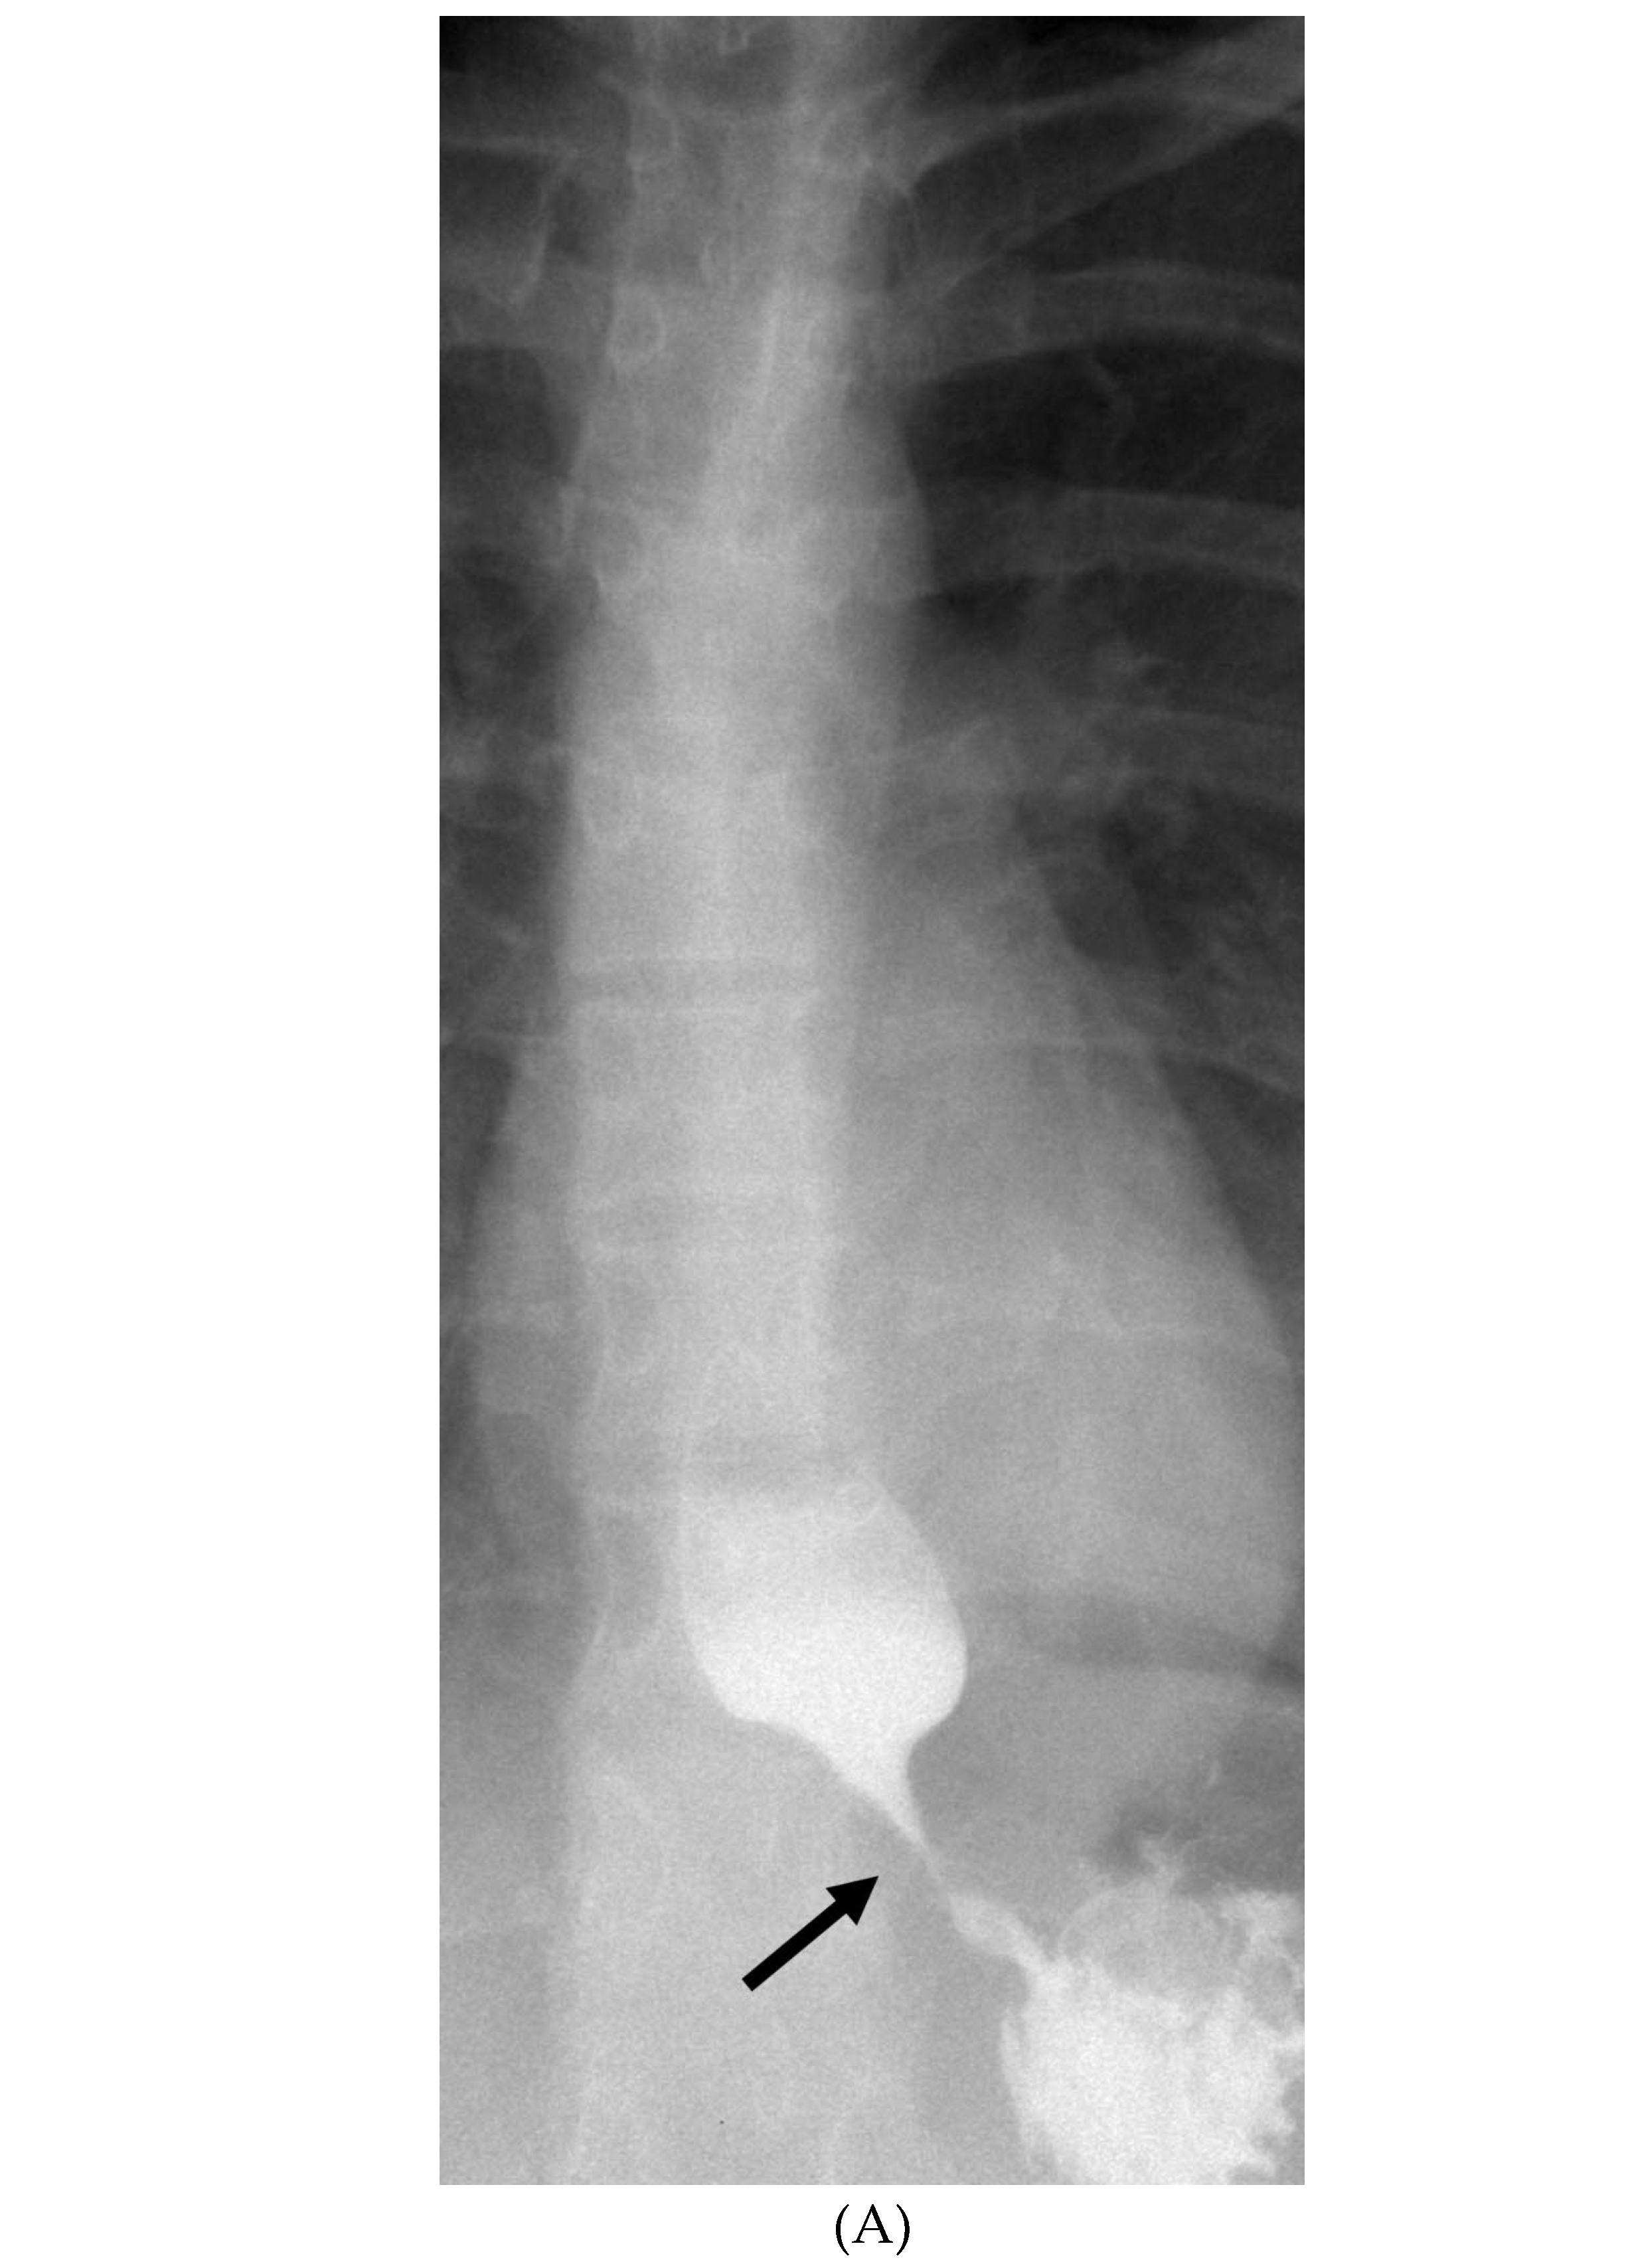

BACTERIAL MENINGITIS

- Vaswani AK, Nizamani WM, Ali M, Aneel G, Shahani BK, Hussain S. Diagnostic Accuracy of Contrast-Enhanced FLAIR Magnetic Resonance Imaging in Diagnosis of Meningitis Correlated with CSF Analysis. ISRN Radiol. 2014 Mar 20;2014:578986. PMID: 24977138; PMCID: PMC4062848. [CrossRef]

- Jaremko JL, Moon AS, Kumbla S. Patterns of complications of neonatal and infant meningitis on MRI by organism: a 10 year review. Eur J Radiol. 2011 Dec;80(3):821-7. Epub 2010 Nov 10. PMID: 21067879. [CrossRef]